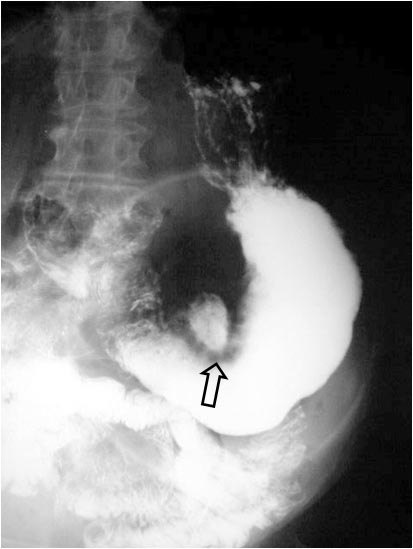

SIGNO DEL HALO O COLLAR ULCEROSO

Signo de úlcera gástrica benigna en el estudio baritado superior (EGD). Tiene el mismo significado que la línea de Hampton, es decir, representa los bordes del nicho ulceroso pero en este caso dichos bordes están edematoso creando un rodete alrededor del cráter que, en el estudio baritado aparece como un halo hipodenso (flecha).